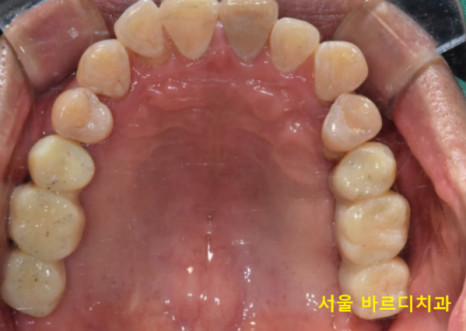

231218

임플란트 뼈이식 흡연을 하시기 때문에

충분히 기다렸습니다.

5월달에 왼쪽 위부터 수술했는데

7개월정도 지나 보철을 올려드렸어요.

240408

7개월이라는 길고 긴 고난의 시간을 겪고

길동 치과에서 치료를 끝내드렸습니다.